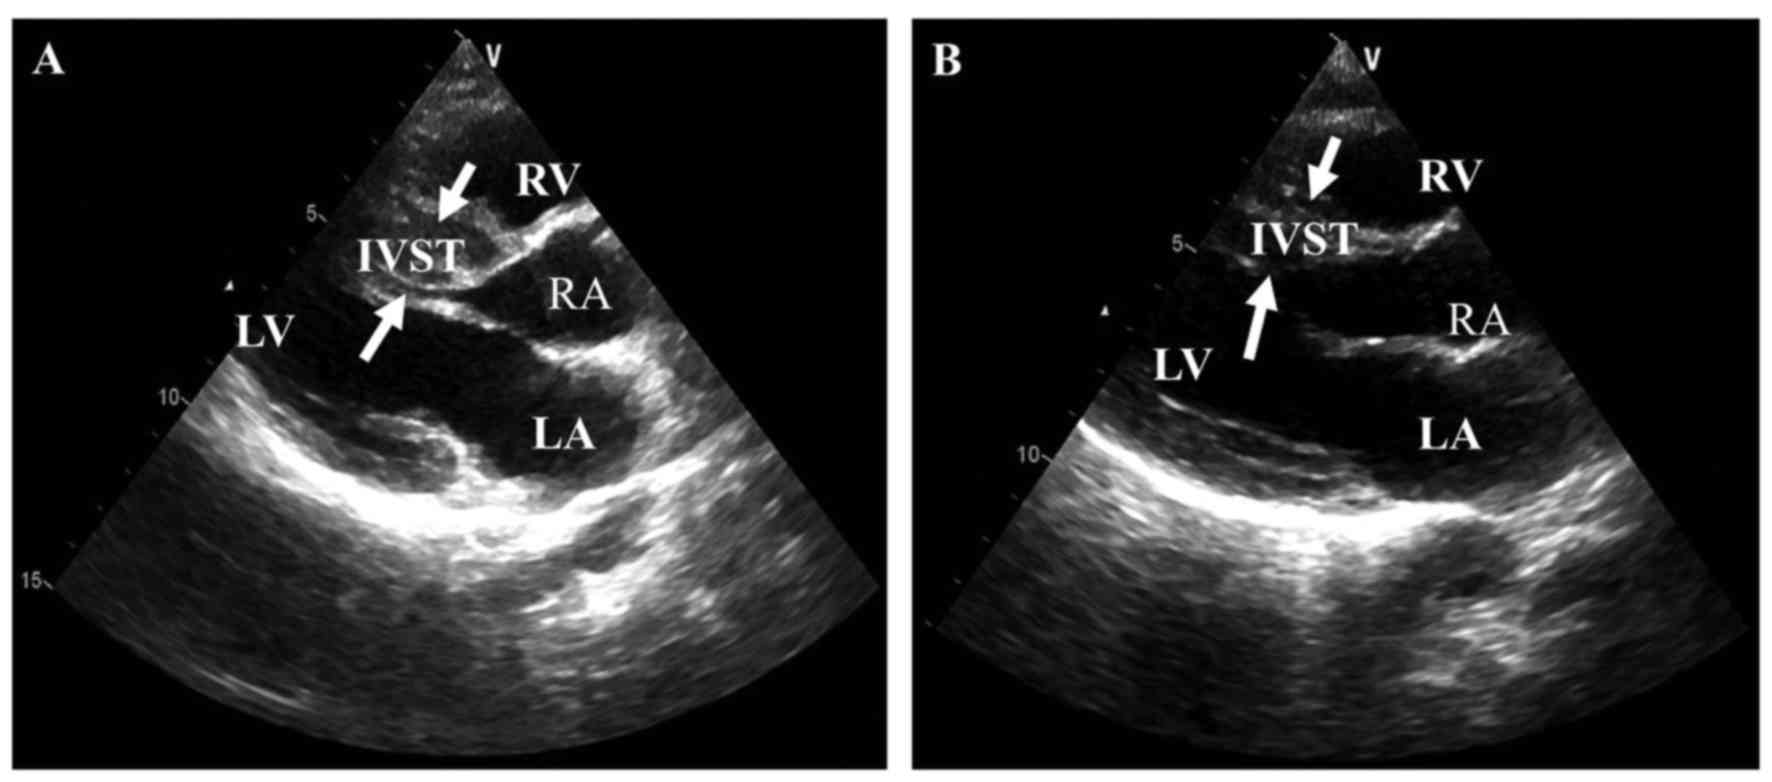

Family A, B and F were of the Han ethnic group; family C, D and E were of the Yi, Naxi and Pumi ethnic groups, respectively. Our results showed that 3 single mutations and 3 double mutations were found in 6 pedigrees with familial HCM (Fig. 2). A 28-year-old male HCM patient, experiencing palpitation and chest tightness, was found to carry a novel mutation (TAZ, p.Ile208Val). A mutation of p.Gln998Glu in MYBPC3 was detected in a proband patient (family A, III:5) who was diagnosed as having HCM at age 34, with intermittent chest tightness and shortness of breath, and a typical thick IVST (22 mm). His 2-year-older sisters were respectively diagnosed as HCM patients at age 36 and 42 years, and his father and grandmother had undergone sudden death. Another proband (family B, II:1) having MYH7 p.Arg858Cys was diagnosed as HCM at age 23 years and experienced chest pain, but his father and mother did not have disease phenotype. More importantly, the third proband (family C, III:1) carrying a double mutation (MYBPC3, p.Gln998Glu plus TNNI3, p.Arg145Gly) had a greater IVST (18.8; >15 mm), and his father, aunt and female cousin were diagnosed with HCM a fewer years ago. A proband (family D, III:1) carrying a double mutation (PRKAG2, p.Gly100Ser plus MYBPC3, p.Lys1209Serfs*28) was diagnosed with HCM at age 26, and his mother and grandmother had undergone sudden cardiac death. A proband (family E, II:1) carrying a double mutation (TNNI3, p.Glu124Gln plus GLA, p.Trp47*) presented with heart failure at age 47 years, and the echocardiography showed that he had a high IVST (Figs. 2 and 3A).

Figure 3

Two-dimensional echocardiography of hypertrophic cardiomyopathy (HCM) patients. (A and B) The echocardiogram of the four chambers of proband family F (patient II: 1) and patient A14, respectively. White arrows indicate areas of hypertrophy.